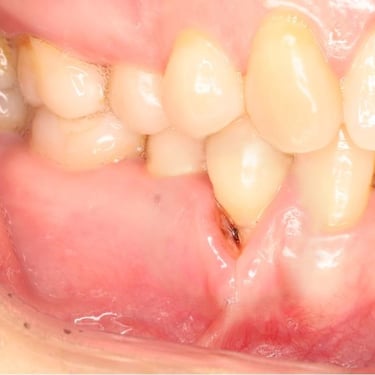

Lesión Endo-Perio Combinada

Una lesión endo-perio combinada es una condición en la que hay tanto una infección de la pulpa como una enfermedad periodontal.

Los pacientes pueden experimentar dolor, hinchazón y movilidad dental.

El tratamiento incluye tanto el tratamiento de conducto como el tratamiento periodontal para abordar ambas infecciones. La coordinación entre el endodoncista y el periodoncista es esencial.